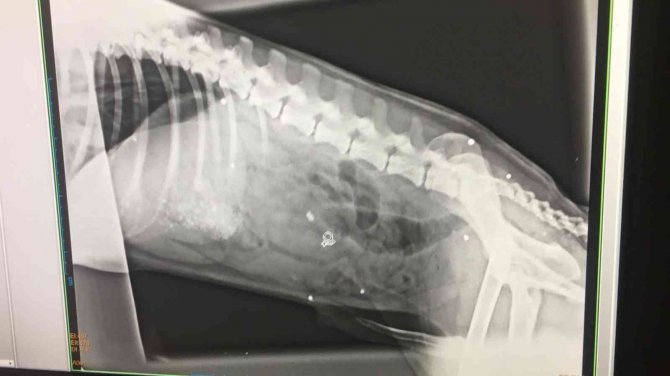

Olay Bandırma'da Yenisığırcı kırsal mahallesinde meydana geldi. Mahallede yaşayan Serap Eken son bir yılda yaklaşık 70'e yakın hayvanın kimliği belirsiz kişiler tarafından zehirlenerek öldürüldüğünü iddia etti. Civarda yapılan araştırmalarda ele geçirilen zehirli sucuk ve mamaları muhafaza altına alarak, incelemeye gönderilmesi ve köpeklere yapılan otopsi raporları doğrultusunda hayvanların kasıtlı olarak öldürüldüğünü söyleyen Eken, "Geçen yıl yaşanan en büyük katliam kendi evimdeki 6 çocuğumun öldürülmesiydi. Karneli çocuklar ve felçli hayvanlar zehirlendi. Zehirli sucuklar bulundu. Bunlar test edildi. Otopsi raporları çıkartıldı. Buna rağmen savcılık soyut delil olarak göstererek mahkeme düştü. Zehirlenen köpeklerin bir kısmını veterinere yetiştirmeye çalıştım. Bazılarını kurtarabildik" dedi.